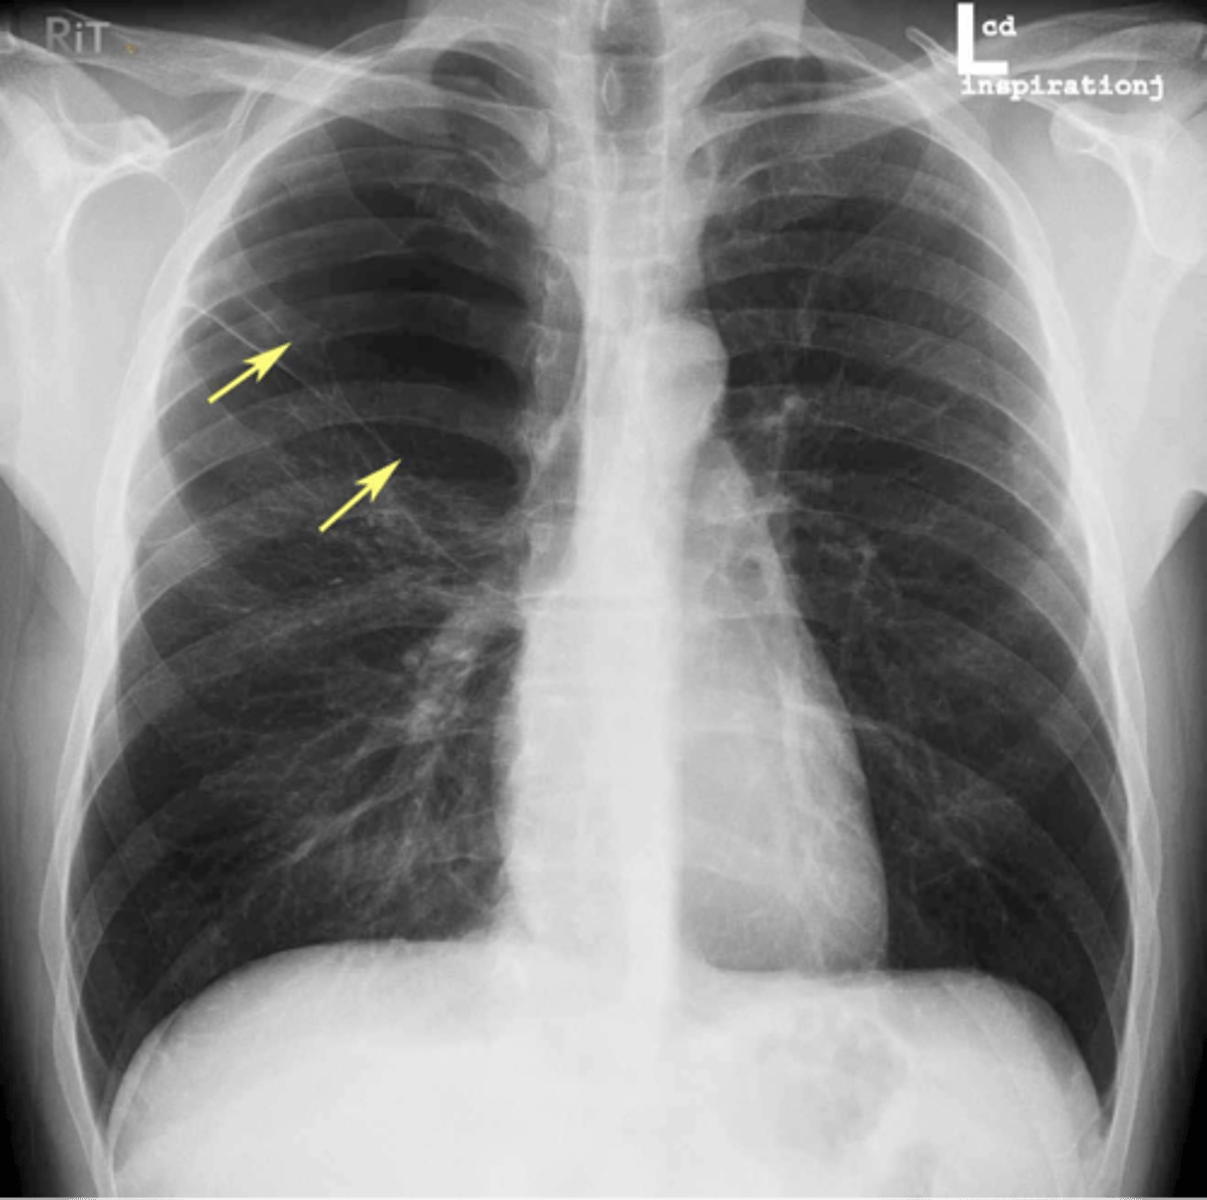

RUL bullae

knowt flashcard image

Bullae RUL